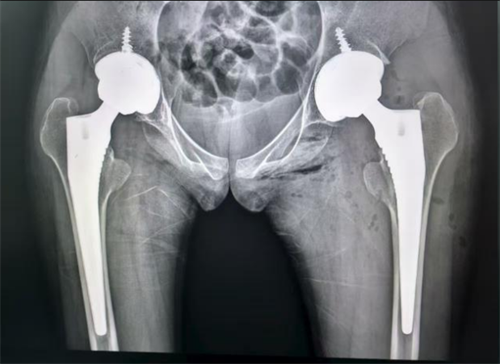

小雨进行右侧髋关节置换术后的X片

经过周密的术前准备,李良军主刀为小雨成功实施了右侧人工全髋关节置换术。术后三天,她在助行器辅助下重新下地行走。右侧髋部持续的剧痛消失了,她再一次感受到了“无痛行走”的喜悦。

小雨进行左侧髋关节置换术后的X片

经过三个月的积极康复,右侧髋关节功能恢复良好,身体状态调整至最佳。今年9月初,李良军主任团队再次为她完成了左侧人工全髋关节置换术。两次手术都非常成功,出血少、恢复快,未出现任何并发症。目前小雨已经完全脱离了轮椅和拐杖,可以独自无痛行走,基本恢复了正常生活。